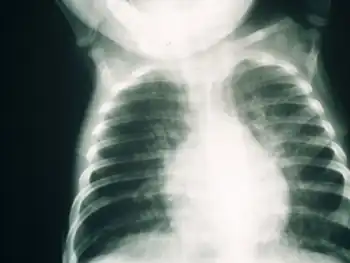

SCID patients are usually affected by severe bacterial, viral, or fungal infections early in life and often present with interstitial lung disease, chronic diarrhea, and failure to thrive.[3] Ear infections, recurrent Pneumocystis jirovecii (previously carinii) pneumonia, and profuse oral candidiasis commonly occur. These babies, if untreated, usually die within one year due to severe, recurrent infections unless they have undergone successful hematopoietic stem cell transplantation or gene therapy in clinical trials.[6]

Early diagnosis of SCID is usually difficult due to the need for advanced screening techniques. Several symptoms may indicate a possibility of SCID in a child, such as a family history of infant death, chronic coughs, hyperinflated lungs, and persistent infections. A full blood lymphocyte count is often considered a reliable manner of diagnosing SCID, but higher lymphocyte counts in childhood may influence results. Clinical diagnosis based on genetic defects is also a possible diagnostic procedure that has been implemented in the UK.[12]

Some SCID can be detected by sequencing fetal DNA if a known history of the disease exists. Otherwise, SCID is not diagnosed until about six months of age, usually indicated by recurrent infections. The delay in detection is because newborns carry their mother's antibodies for the first few weeks of life and SCID babies look normal.